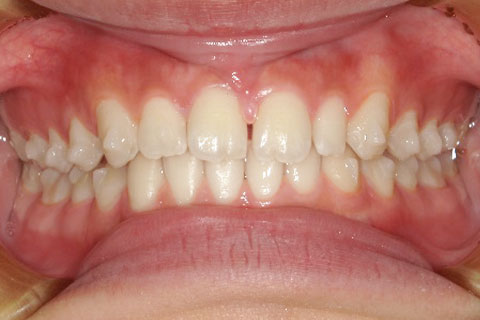

主訴:上下の歯並びのガタガタが気になる

診断名:上下顎叢生

症状:上下顎叢生

患者プロフィール:北九州市・小倉北区30代女性

治療方針:非抜歯治療

治療装置:マウスピース型矯正治療(インビザライン)

抜歯:無し

治療期間:一年半

通院回数:30回

リテーナー:上顎プレートタイプリテーナー 下顎フィクスタイプリテーナー

治療費用:検査診断料(20,000)+装置料金(500,000)+管理調整料(150,000) +装置撤去時診断料(10,000) +保定装置料金(20,000)=700,000(消費税込)

リスク副作用:痛み・治療後の後戻り・歯根吸収・歯髄壊死

詳しい症例説明:この患者さんはガタガタが気になり来院されました。マウスピースタイプの矯正装置で比較的短期間で治療を終えることができました。インビザライン(マウスピース矯正治療)で矯正治療を行うことで取り外して食事ができ、痛みもそれほど感じなかったとのことです。